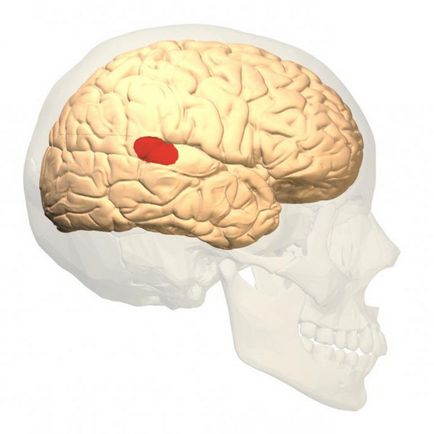

zona Wernicke

Această zonă este un motiv ulterior este descrisă într-un articol pe site-ul menționat mai sus, deoarece este folosit mai ales pentru a înțelege și a „digera“ informația. În cazul în care zona Broca este în proporție de frunte în emisfera stângă, zona Wernicke poate fi amplasat fie în dreapta sau în emisfera stângă în zona verhnevisochnoy.